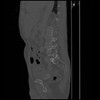

7 CUERPO,CE,Sagittal,3.000,CUERPO,Sagittal,